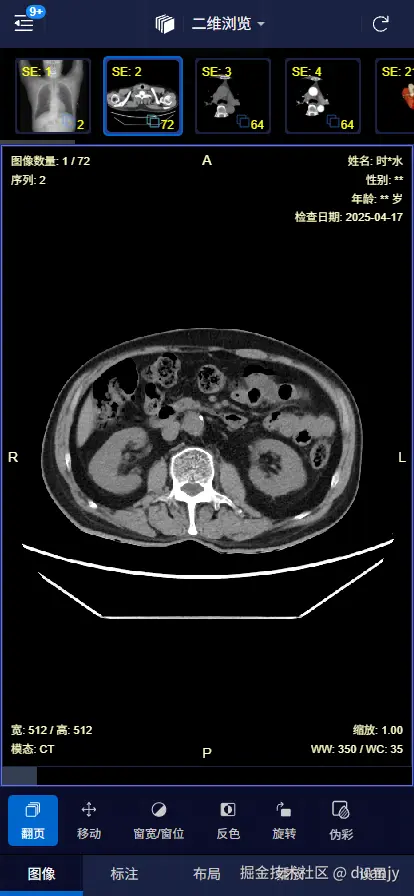

1. PC端 – 二维平片

screenshot.png

支持在 PC 和手机端 打开,可以查看 二维平片三维重建